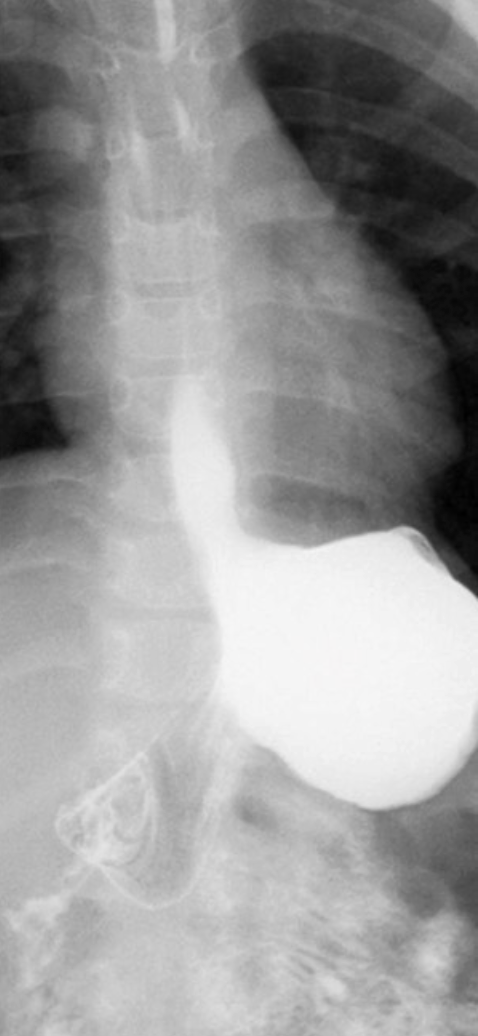

what is a hiatus hernia

when the diaphragm bulges through the diaphragm and into the chest cavity

weakened phreno-esophageal ligament allows for a portion of the stomach to slip through the esophageal hiatus of the diaphragm and into the thoracic cavity.

phreno-esophageal ligament weakens, may dilate, allows for the stomach to slip through the esophageal hiatus

sliding HH = slides freely thru esophageal hiatus (certain actions or movements like coughing can help show the pathology)

paraesophageal HH = a portion of the stomach remains above the diaphragm at all times (no sliding)

RA of HH CXR

large HH can show on CXR as a mass behind the mediastinum

RA of HH on BS or UGI

barium swallow and UGI will show smooth esophagus and stomach with rugae patterns (roughened structure above diaphragm)